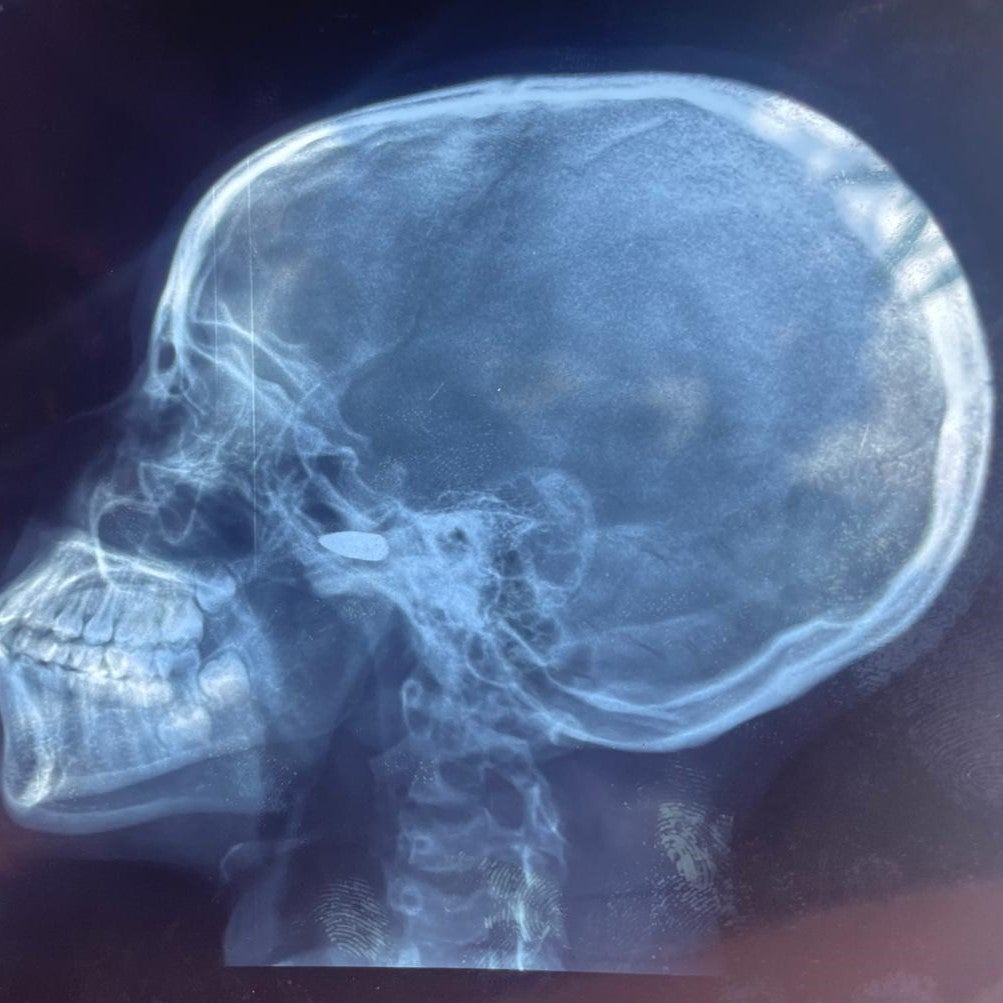

Radiographie d'une fille de 15 ans qui a été touchée à la tête par une balle perdue à Bébédja, au sud du Tchad, le 9 mai 2024, après l'annonce des résultats provisoires de l'election présidentielle au Tchad.

© 2024 Private